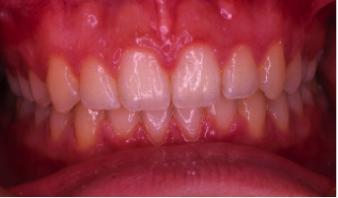

外科矯正治療(はんたいこうごう)

21歳/女性

悩み:顎の曲がりと下顎のでっぱり

下の顎が変形し、上の歯が下の歯より前に出ている状態

治療期間:約2年

治療前

治療後

矯正治療と外科手術を併用して行った患者さんです。

「早い治療計画」での依頼のため、歯を抜かずに矯正治療を10ヶ月行い手術という事になりました。

その後6ヶ月の術後矯正にて終了となりました。

手術も含めて早期治療が目的の患者さんでしたので満足されてよかったです。